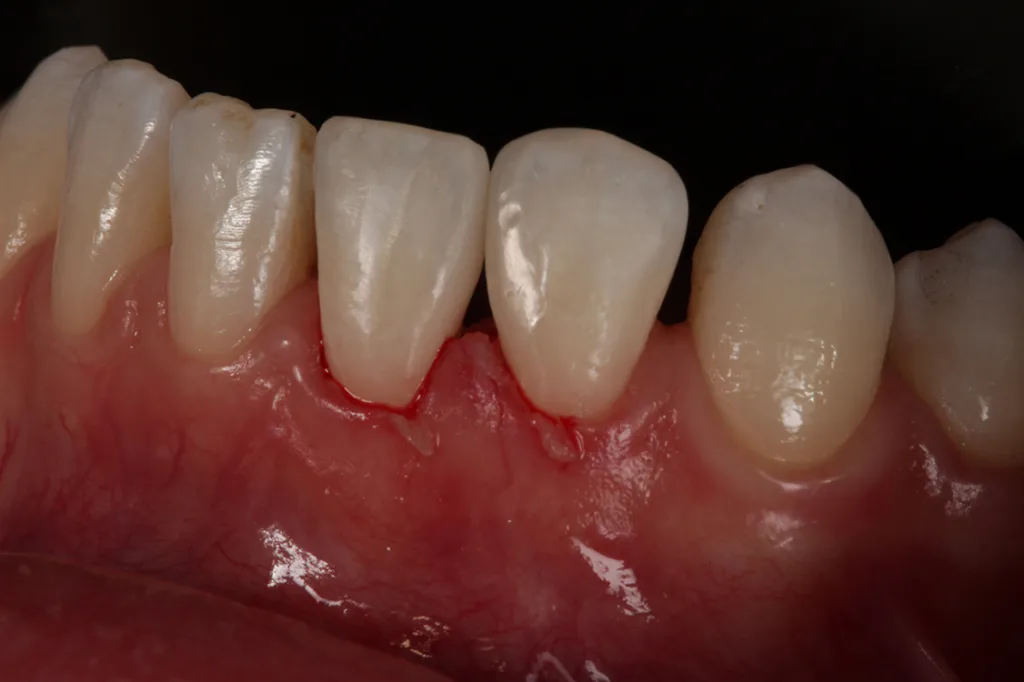

Es zeigen sich postoperativ leichte Irritationen der Gingiva, die durch das Legen der Retraktionsfäden/Ligaturen entstanden sind und sich nach Abheilung und Reifung im Interdentalbereich noch adäquat ausformen werden, um somit einem ansprechenden dentogingivalen Erscheinungsbild zu entsprechen.

Die Zahnform der beiden unteren Schneidezähne 31 und 32 entspricht nach Diastemaschluss nun den Wünschen der Patientin (Abb. 10).

Die Zahnproportionen 31/32 erscheinen nach Aufbau mit Komposit insbesondere im mesiodistalen Bereich etwas „ausgeprägter“ im Vergleich zur kontralateralen Seite und sollten daher als Kompromiss betrachtet werden. Die leicht eingekerbten/gezackten Inzisalkanten wünschte sich die Patientin etwas geradliniger.